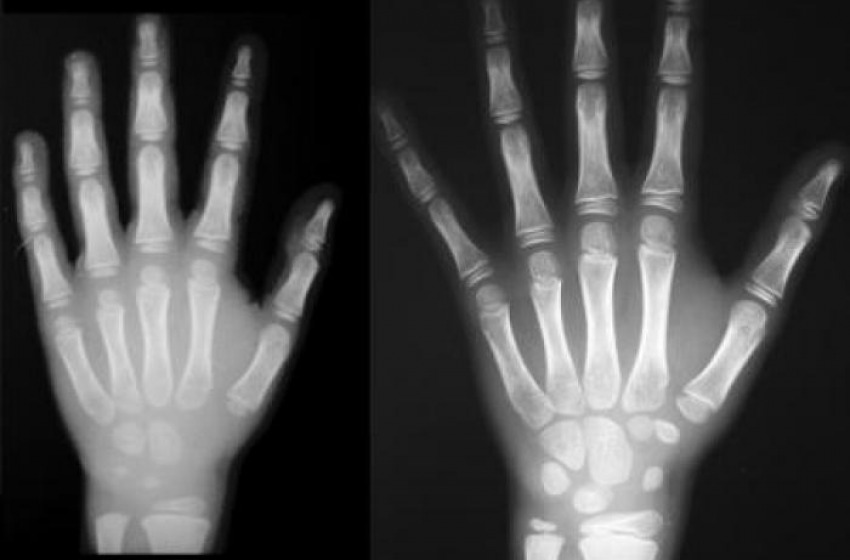

Finto minorenne smascherato con la radiografia del polso

VOLEVA FARE IL FURBO. Si faceva passare per minorenne approfittando dell'aspetto giovanile e, per dimostrarlo, aveva presentato documenti...